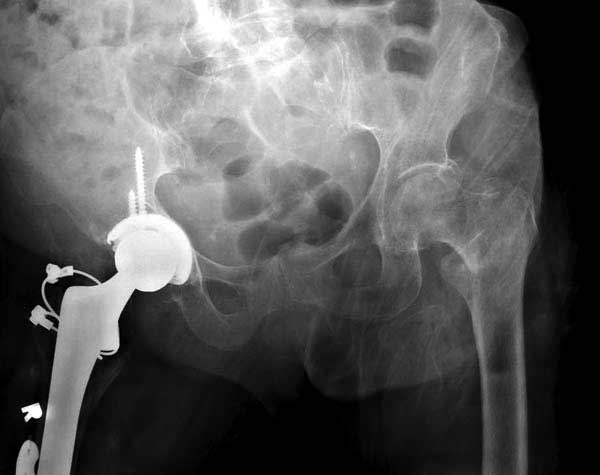

Третья операция-продолжения усилии “синьорами пэрами” по разрушению нормальной анатомии. Крест на головку! По видимому возраст позволяет биполярную конструкции, и при дефекте  calcar пошли на обычный цементный. Ягодичные мышцы потеряли связь с вертелом, т.е. отсутствует верхний удержатель, и результат “a Big Screw Up!” Снимки вызывают головокружение!

Если хирурги не устали от своих “творчеств”, тогда можно ре-оперировать с calcar replacement stem, и собрать остаток ягодичных мышц. Глубина и отстутствие артроза позволяет применить любой, биполярный или тотальный, хотя принять решение можно после ревизии ацетабулума.